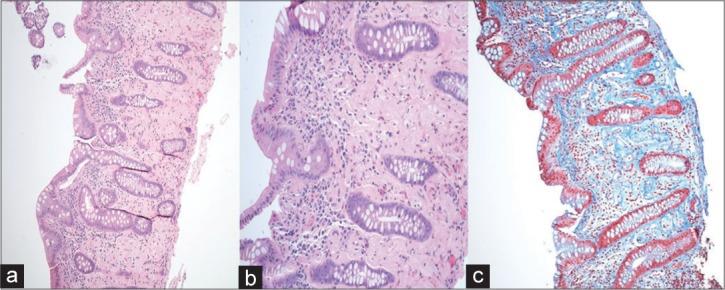

Phlebosclerotic Colitis is a rare, potentially life-threatening condition of unclear etio-pathogenesis seen almost exclusively in Asians and people of Asian descent. The condition predominantly affects the right hemicolon and imaging plays a crucial role in its diagnosis. Here we report the only second documented case of phlebosclerotic colitis in North America in a 60-year-old Canadian resident of Vietnamese descent with a history of consuming herbal medication () in soup for 2-3 decades.

静脉硬化性结肠炎是一种罕见的、可能危及生命的疾病,其病因和发病机制尚不清楚,几乎仅见于亚洲人和亚裔人群。该病主要影响右半结肠,影像学检查在其诊断中起着关键作用。在此,我们报告北美第二例有记录的静脉硬化性结肠炎病例,患者为一名60岁的加拿大越南裔居民,有2至3十年在汤中食用草药的病史。